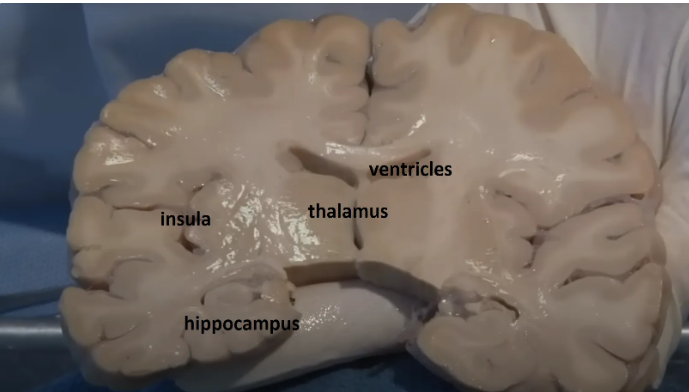

Thalamus (pink) and hypothalamus (yellow): their medial surfaces border the third ventricle (blue).

Overlaying the green cingulate and parahippocampal gyri with the purple hippocampus highlights the limbic lobe. Yellow = fornix. Brownish pink = hypothalamus

The purple hippocampus is visualized tracing the ventricular system (turquoise).